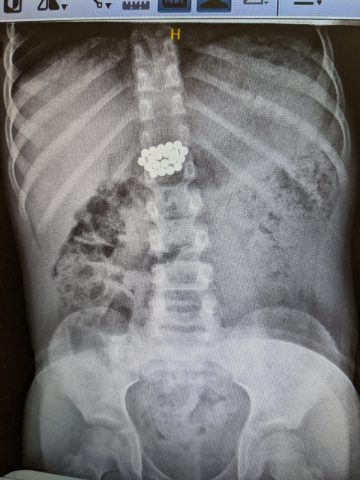

בן ה-8 הגיע למרכז רפואי מאיר מקבוצת כללית לאחר שבלע למעלה מ-20 מגנטים.

ד"ר אייל זיפמן, מנהל השירות לגסטרואנטרולוגיה ילדים מסביר: "בגלל ההבנה לגבי הנזק שמגנטים עלולים לחולל – והחשש מנקב במעי וזיהום בחלל הבטן, הוחלט לשלוח את הילד באופן מידי לצילום. בצילום נצפו המגנטים במעי הדק במקום שלא ניתן להגיע ללא ניתוח. הוחלט כי נעשה מעקב לבחון את מקומם ובשלב מסוים נמצא כי הם אינם מתקדמים לבד ויש לעשות קולונוסקופיה. המגנטים נמצאו במעי הגס והוצאו בהצלחה".